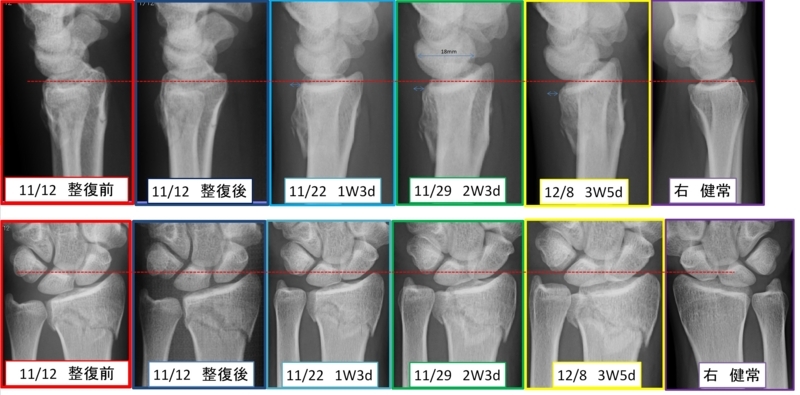

11/12 10:15

左橈骨遠位端骨折と診断、転位あり通称コーレス骨折。

11/22 10日目(1W3d)

つきで整形外科受診、ずれはないとの事

11/29 17日目(2W3d)

つきで整形外科受診、ずれは許容内との事

12/8 26日目(3W5d)

つきで整形外科受診、ずれ有との事

熊本整形外科も紹介してくれ手の専門医にも確認

4Wを考慮すると保存、手術一長一短。保存を選択。